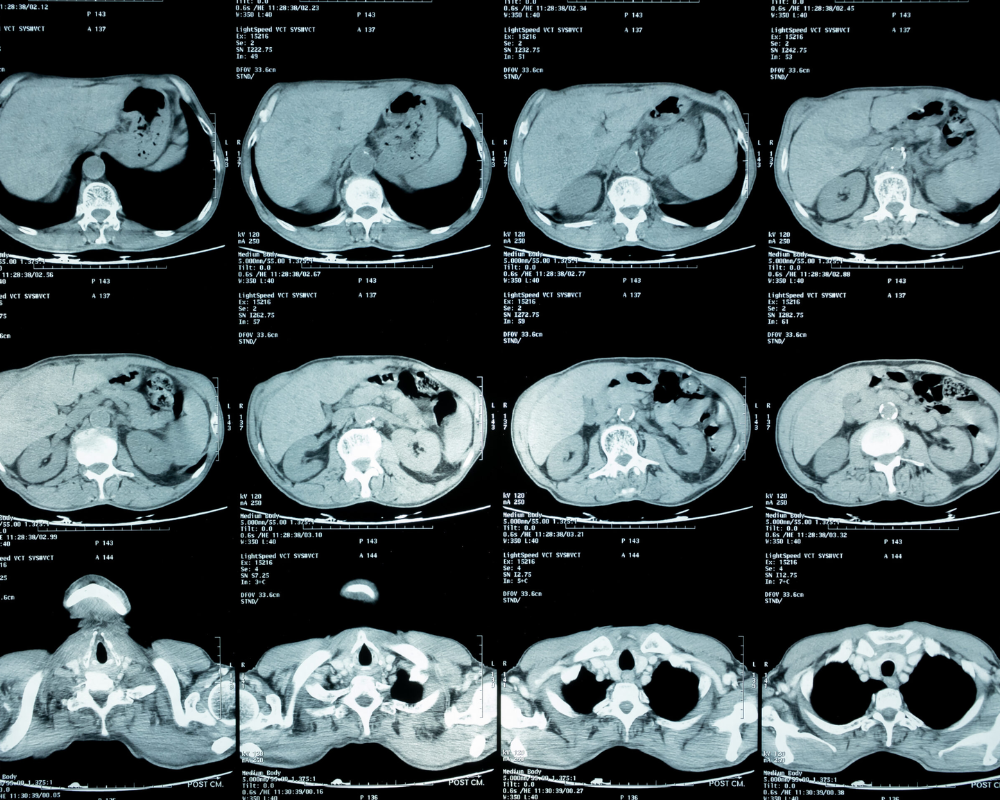

Ongoing stomach pain, swelling, digestive concerns, or abnormal test results often need more than a basic scan to understand what is going on. Our Abdominal MRI in Houston TX provides detailed imaging of organs and soft tissues in the abdomen, helping your doctor look more closely at the liver, pancreas, kidneys, gallbladder, spleen, and surrounding areas. It may be recommended when a more detailed view is needed for diagnosis, follow-up, or treatment planning. We also serve patients looking for an Abdominal MRI in Richmond TX, offering the same level of comfort, accuracy, and reliable imaging experience.

At Maximum Resolution Imaging Center, our Abdominal MRI in Houston TX is used when your provider needs a clearer view of internal organs that cannot be fully understood through basic imaging. This includes areas such as the liver, pancreas, kidneys, gallbladder, and abdominal soft tissues. It is often recommended when symptoms, lab results, or prior scans require a more detailed look to better understand what is happening inside the body. Patients scheduling an Abdominal MRI in Richmond TX receive the same level of attention and imaging accuracy.

Each Abdominal MRI Scan is performed using advanced imaging techniques designed to capture fine detail without making the process difficult for the patient. Depending on your case, your provider may request an Abdominal MRI with contrast or an Abdominal MRI without contrast to highlight specific areas more clearly. Our 3T MRI system helps improve image clarity, especially when examining small structures or complex conditions. Whether you are coming in for an Abdominal MRI in Houston TX or from nearby areas including Richmond, the focus remains on delivering clear results that help guide the next step in care.